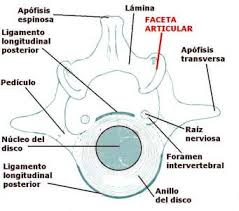

377 × 297 - gimolimpo.com

{"id":"bC9UzXdTekQ09M:","isu":"gimolimpo.com","itg":0,"ity":"jpg","oh":297,"ou":"http://www.gimolimpo.com/Paginas/lesiones%20en%20el%20deporte_archivos/image004.jpg","ow":377,"pt":"OLIMPO

GYM","rid":"Ab3Tv6Utj7z5kM","rmt":0,"rt":0,"ru":"http://www.gimolimpo.com/Paginas/lesiones%20en%20el%20deporte.htm","s":"Columna

cervical Oseas Lesiones por flexión. Subluxación anterior. Subluxación

bilateral facetaria. Fractura por acuñamiento anterior del cuerpo

vertebral.","sc":1,"th":199,"tu":"https://encrypted-tbn0.gstatic.com/images?q\u003dtbn:ANd9GcTcrrYTwk4il3WFRg-ZshV3-n7HqnZ89UTT6wB6cnUv6Vgxr7P6RQ","tw":253}